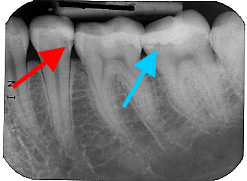

Foto vom Zahn 37 mit Karies

Foto des Zahnes 37 der selben Patientin

Hier sehen Sie wie es unter einer neuen, weißen Zahnfüllung aussehen kann, die eine Hilfskraft vorZahnröntgen mit Karies einer Woche gemacht hat. Die Patientin kam wegen arger Zahnschmerzen zu uns und im Röntgenbild konnte man unter der Füllung die Karies sehen. Das selbe traf auf einen zweiten Zahn zu. Alle Versuche die Situation zu retten blieben erfolglos und beide Zähne mußten wurzelbehandelt werden, um der Schmerzen Herr zu werden.